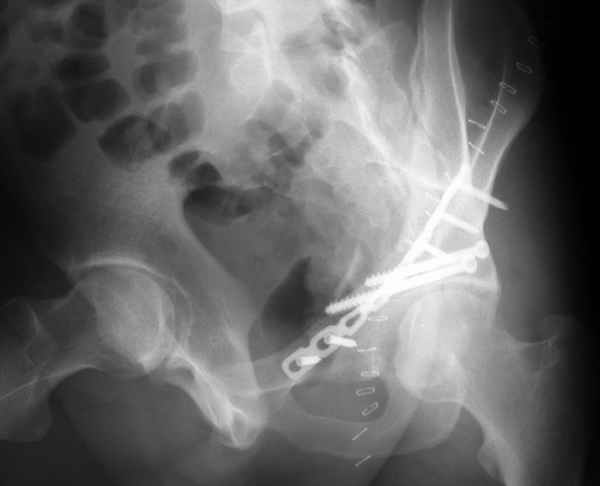

Разрушения оказались более обширные чем видно ра рентгенограмме. Только пять фрагментов с суставной поверхностью, два почти свободных. Послеоперационная картинка в цифре отсутствует, да она и не очень красивая. Удалось собрать суставную поверхность, много осколков без хряща на передне внутренней поверхности остались сами по себе, передние отделы теза синтезировал. Против обыкновения оставил больную на вытяжении.

Конечно изнутри таза массивная гиперпластическая мозоль - пришлось немного попотеть и интерпозиция по плоскости перелома. Хорошо был виден ствол нерва с внутренней стороны вырезки - сделали блокаду, как положено. После операции движения стопы в полном объеме чувствительных расстройств нет. Репозиция удалась - мы были в легкой эйфории - внесуставной доступ и т.д. Через сутки стопа повисла - грубых выпадений на ЭНМГ нет, но тем не менее ишемический неврит малоберцовой порции седалищного нерва - бич застарелых повреждений.

Ах если бы Русские люди не обманывали себя и больных, а направляли бы срочно в специализированные отделения, то можно было бы получить хороший результат куда меньшей кровью пациентов и сердечных ран хирургов. Посылаю еще два снимка. Привет ЛАФ.